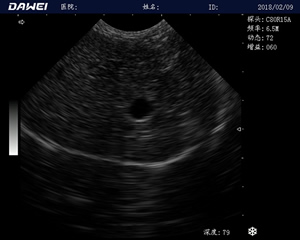

MT15獸用B超機適用探頭

適用對象:

牛羊馬豬犬貓及多種家禽、實驗動物、野生動物、及部分水生動物

應用范圍:

中小動物的肝、膽,脾、腎、膀胱、子宮、妊娠等各組織器官的檢查和病變的診斷